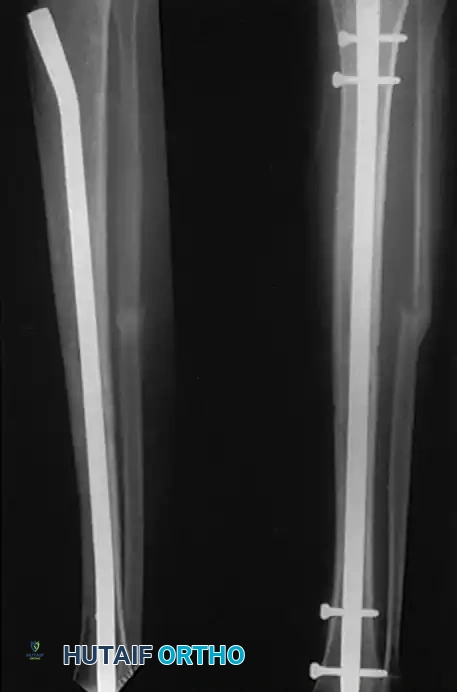

Intramedullary Fixation of Tibial Shaft Fractures

Locked intramedullary (IM) nailing is universally recognized as the gold standard and treatment of choice for the vast majority of type I, type II, and type IIIA open, as well as closed, tibial shaft fractures.

IM nailing offers superior biomechanical advantages by acting as a load-sharing device positioned at the mechanical axis of the bone. This minimizes bending moments compared to eccentrically placed plates. Furthermore, IM nailing preserves the critical soft tissue sleeve and periosteal blood supply around the fracture site, promoting secondary bone healing via callus formation and allowing for early mobilization of adjacent joints.

The ability to lock the nails proximally and distally provides absolute control over length, alignment, and rotation in unstable, comminuted, or segmental fractures. Modern interlocking designs permit the stabilization of fractures located as far proximal as the tibial tubercle or as far distal as 3 to 4 cm proximal to the ankle joint plafond.

* Closed Fractures: Reamed IM nailing is the definitive treatment of choice. Meta-analyses and landmark trials, such as the SPRINT (Study to Prospectively Evaluate Reamed Intramedullary Nails in Patients with Tibial Fractures) study, have demonstrated a statistically significant decrease in nonunion rates and secondary interventions with reamed nails in closed injuries.

For IM Nailing:

One of the primary benefits of IM nailing is the ability to initiate early mobilization. Patients are encouraged to begin active and active-assisted range of motion exercises of the knee and ankle immediately postoperatively. Depending on the fracture pattern (e.g., axially stable transverse fractures), patients may be allowed weight-bearing as tolerated immediately. For axially unstable or highly comminuted fractures, weight-bearing may be restricted initially, though the load-sharing nature of the nail generally allows for a faster return to full weight-bearing compared to plate fixation.